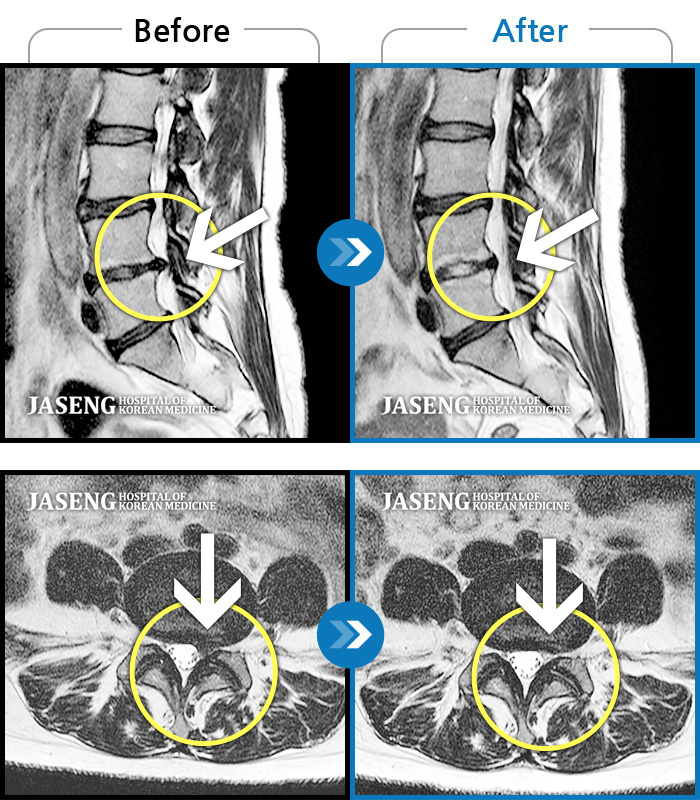

MRI 치료사례

반복적 업무 후 시작된 요통 왼쪽다리 방사통과 발가락의 감각저하로 내원